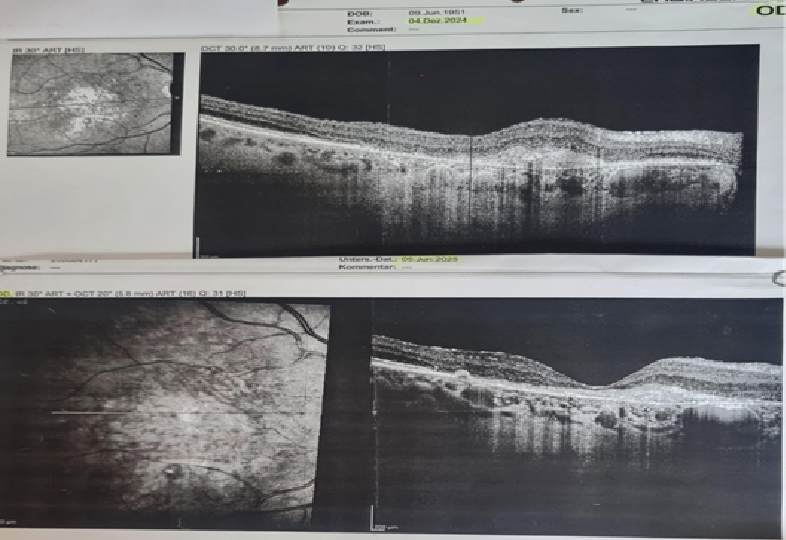

OCT – Vergleich der feuchten-, trockenen Makuladegeneration und Makulaloch.

Beispiele mit Bildern jeweils vor und nach erfolgreicher Behandlung.

Patient 66 Jahre alt und litt an feuchter und trockener altersbedingter AMD. Bilder von linkem und rechten Auge jeweils vorher und nacher. Nach einer 10 monatigen Behandlung mit chinesischer Medizin verbesserte sich sein Zustand deutlich. Die feuchte und trockene Makuladegeneration der Augen  verschwanden praktisch. Das zentrale Sehvermögen beider Augen verbesserte sich deutlich.